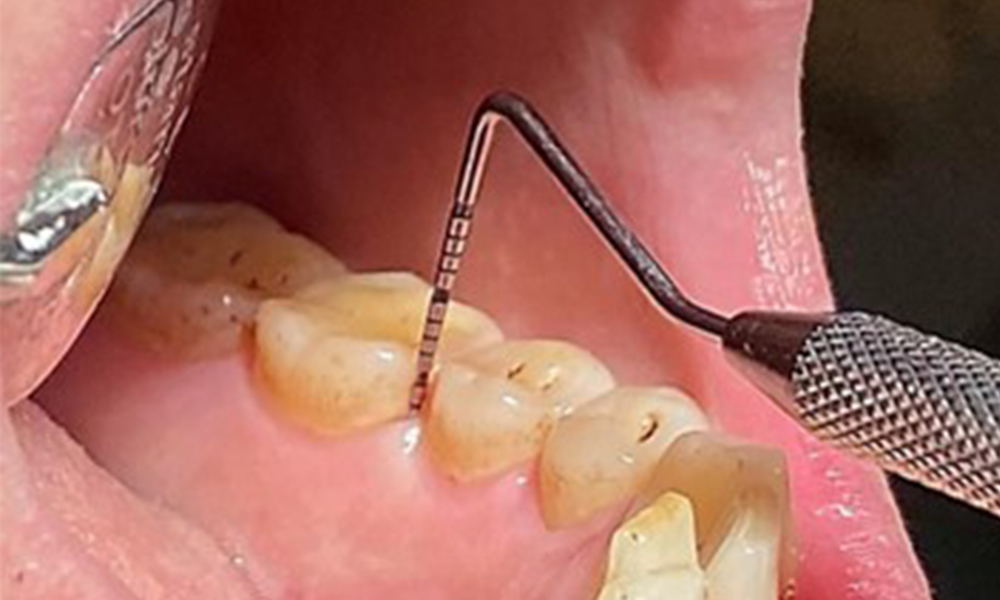

Aufgrund des guten allgemeinmedizinischen Zustandes ist der aus der Mundgesundheit ermittelte Bedarf maßgebend für die Behandlung. Die regelmäßige Erhebung der Sondierungstiefen ist unabdingbar. Die gingivale Blutung ist bei Rauchern herabgesetzt, weswegen die klinische

Diagnose einer Parodontitis nur durch Sondierung möglich ist (Abb. 7). Die ausschließliche Erhebung von Blutungsindizes verdecken unter Umständen das Bild einer bestehenden Parodontitis oder Gingivitis. (5)